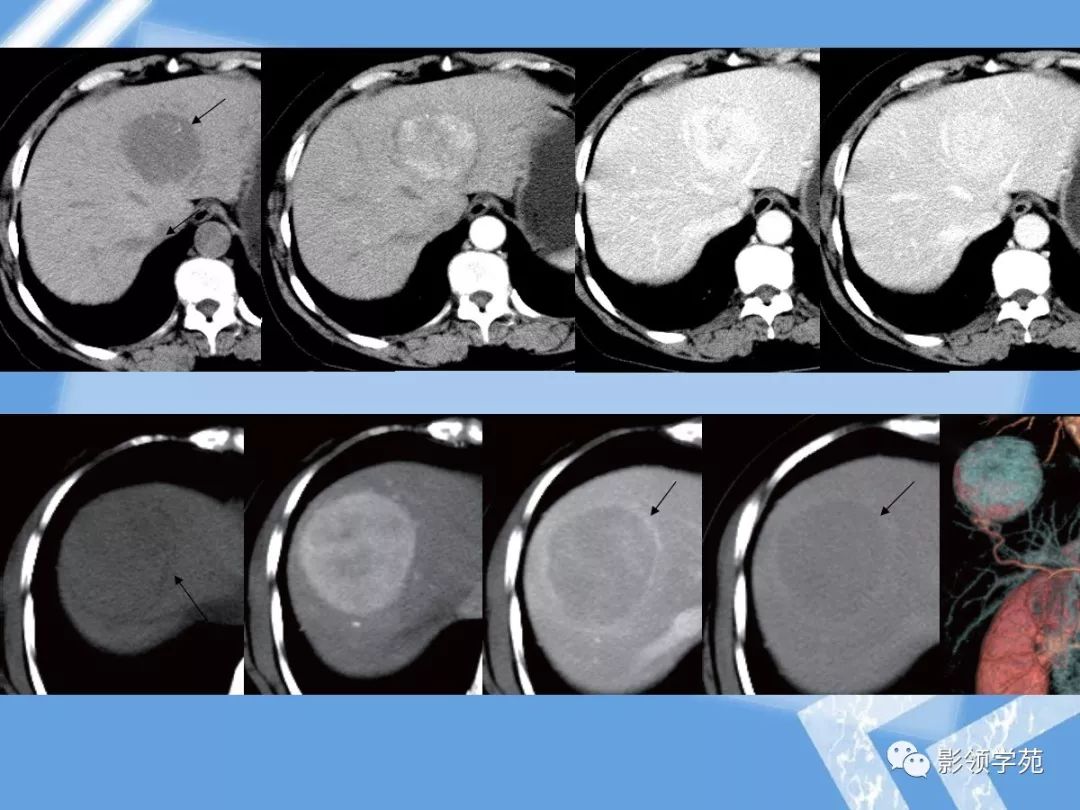

14种常见肝脏良恶性肿瘤图解

22种肝脏少见及不典型肿瘤的影像表现